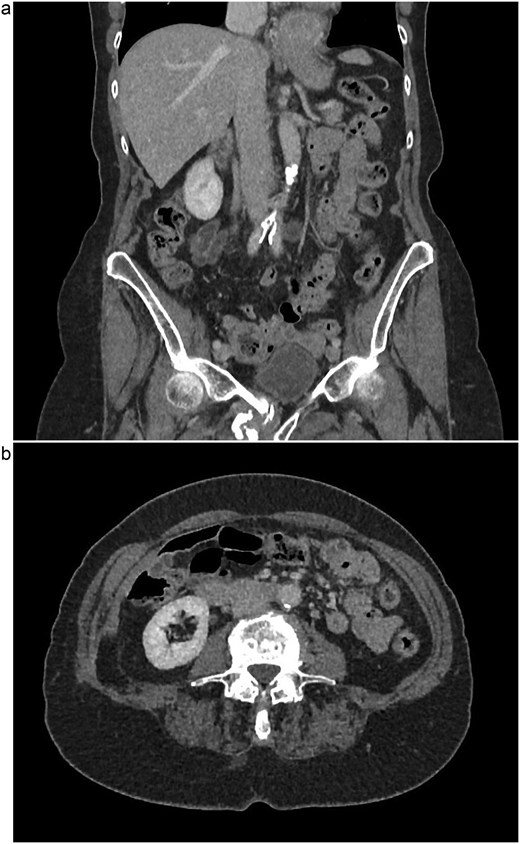

The patient is a 75-year-old female with no relevant past medical or surgical history who underwent an L4-L5 extreme lateral interbody fusion (XLIF) at an outside surgical center. During the procedure, a significant amount of blood loss from an undetermined bleeding vessel was encountered. The primary surgeon injected Surgiflo and Gelfoam to attempt to obtain hemostasis. The XLIF was completed with an estimated blood loss of greater than 2 l. In the post-anesthesia care unit (PACU), the patient remained hypotensive. Two units of packed red blood cells, phenylephrine, 5 l of crystalloid, and 50 g of albumin were administered in the PACU and the patient was transferred to a surgical intensive care unit at a level one trauma center. A computed tomography (CT) scan was obtained which demonstrated a thrombus present in the inferior vena cava (IVC) extending to the left common iliac vein (Fig. 1a and b). She received an additional unit of packed red blood cells and blood pressure support was maintained with norepinephrine. Vascular surgery was consulted. At the time of evaluation, the patient had remarkably improved hemodynamics and was on minimal pressor support. After discussion of risks and benefits of intervention versus medical management, the vascular team recommended therapeutic anticoagulation with continuous intravenous heparin. The patient was observed in the intensive care unit for 2 days until she was off pressor support. She was started on apixaban once her hemoglobin was stable on three consecutive blood draws. A repeat CT angiogram 1 month after discharge demonstrated near resolution with a small residual thrombus in the left common iliac vein (Fig. 2a and b). She has returned to normal activity and will remain on apixaban for 6 months after the inciting event and the thrombus will be evaluated again for further evolution.

(a) Coronal view of resolved thrombus, 5 months post-op. (b) Axial view of resolved thrombus, 5 months post-op.